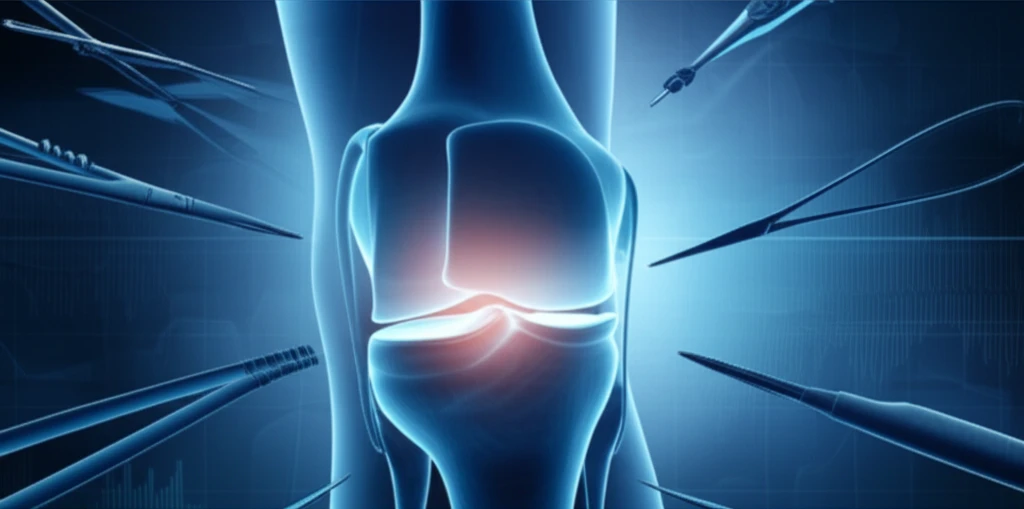

Meniscus Repair Revolution: Is All-Inside Surgery Right for You?

"Discover the latest advancements in all-inside meniscus repair for posterior third tears, offering a potentially safer and more efficient alternative to traditional methods."

All-inside repair techniques are rapidly changing how surgeons approach complex meniscus issues. These modern methods often provide a safer, more efficient, and less invasive alternative to traditional inside-out repair, especially for those tricky posterior third tears.